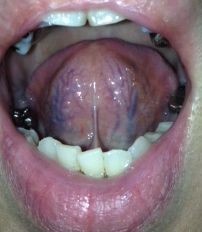

¡Ú2013ǯ10·î16Æü´ÁÊýÌôÉþÍÑÁ°¤ÎÀå¤Îɽ¡Û

¡Ú2013ǯ10·î16Æü´ÁÊýÌôÉþÍÑÁ°¤ÎÀå¤Î΢¡Û